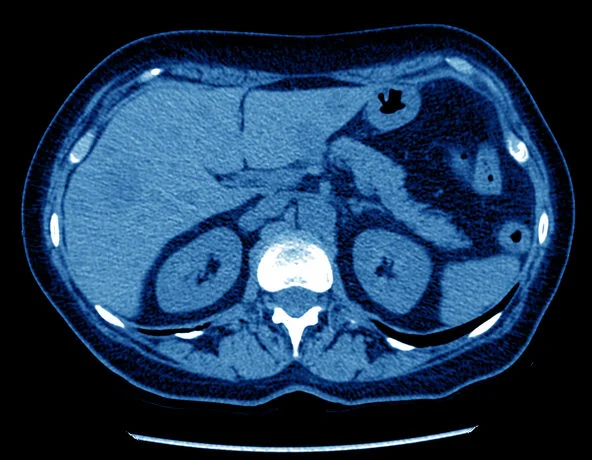

و غالبًا ما تشخص باستخدام الأشعة المقطعية “CT” أو الرنين المغناطيسى “MRI” بالصبغة ثلاثية المراحل, و تبين تلك الأشعات التشخيصية المعلومات اللازمة عن التكتلات الموجودة داخل الكبد من حيث عددها و حجمها و خصائصها الخارجية و مدى انتشارها.

قبل أن نتكلم عن هذه التقية الحديثة , يجب أولا أن تعرف طبيعة الغذاء الدموى الفريد للكبد: الكبد يختلف عن معظم أعضاء الجسم التى يصلها الدم عن طريق مصدر واحد. يصل الدم المحمل بالأكسجين للكبد عن طريق مصدرين و هما الشريان الكبدى “hepatic artery” و الوريد البابى الكبدى “portal vein”, ثم يخرج الدم المحمل بثانى أكسيد الكربون لخارج الكبد عن طريق الوريد الكبدى “hepatic vein”و يعتمد العلاج بالاصمام على هذا المفهوم , حيث يقوم طبيب الأشعة التداخلية بادخال قسطرة شريانية دقيقة حتى المصدر الذى يوصل الدم لخلايا الورم و يقوم بحقن مادة لسد هذا المصدر. و بالتالى تموت الخلايا السرطانية التى تتغذى من هذا الشريان , بينما باقى أنسجة الكبد يصلها الدم المؤكسد بشكل طبيعى عن طريق الوريد البابى الكبدى. و يمثل هذا العلاج خيار جيد للمرضى الغير مناسبين للجراحة و الاستئصال الموضعى و مع الأورام الكبيرة نسبيا ” أكبر من 5 سم “. و لا يحتاج المريض يعد إجراء الاصمام للمكوث بالمستشفى و يخرج بنفس اليوم.